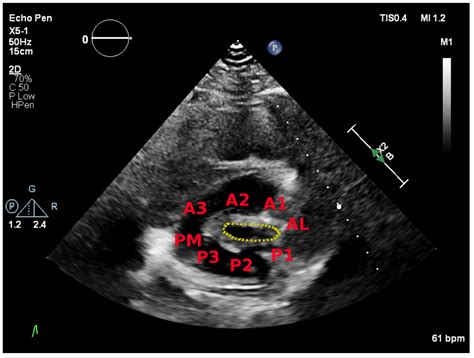

When interpreting the results of a *mitral stenosis echo*, cardiologists look for several key indicators:

Valve Morphology: The shape and structure of the mitral valve are examined to determine the extent of narrowing and any signs of calcification or thickening.

Valve Area: The area of the mitral valve opening is measured. A normal valve area is typically around 4-6 cm². In mitral stenosis, this area is significantly reduced, often to less than 2 cm².